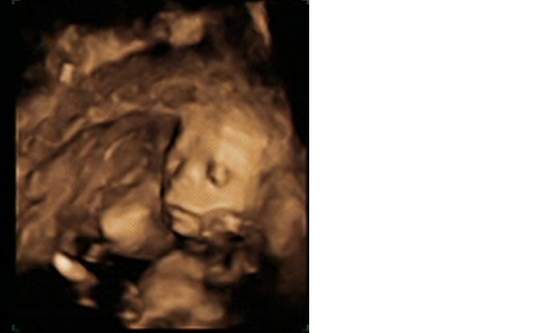

Oto zdjecia mojej Oleńki:-)